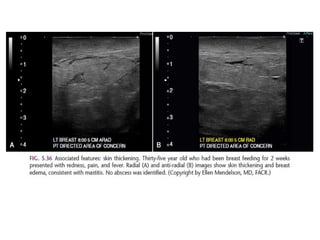

Typically benign

Skin, vascular, coarse, large rod like, round or punctate

(< 1mm), rim, dystrophic, milk of calcium and suture

calcifications are typically benign.